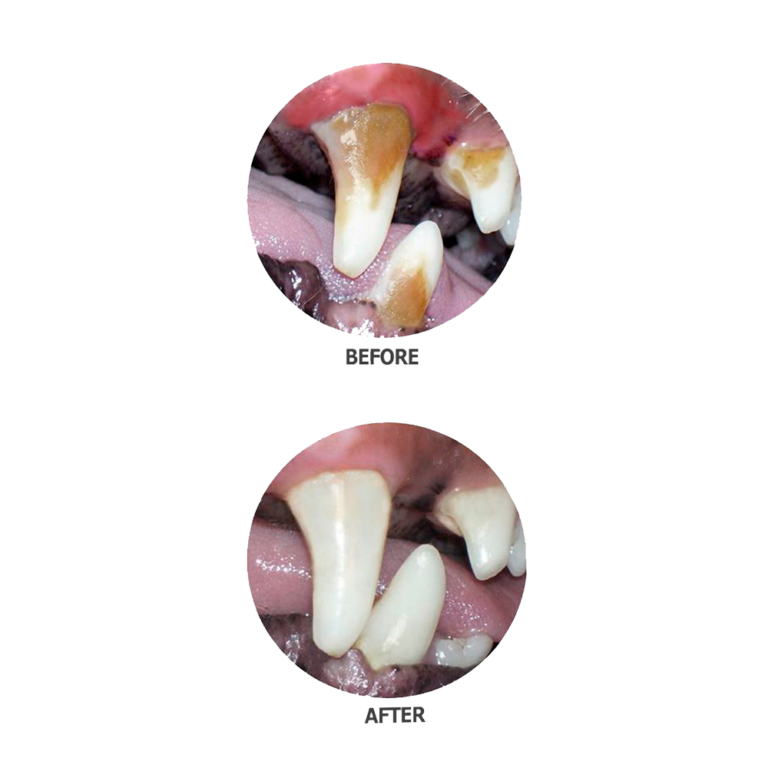

- Then tooth scaling will be performed, using both hand and ultrasonic scalers to remove plaque and tartar above and below the gum line. The tartar below the gum line causes the most significant periodontal disease, so it is important that it be thoroughly removed.

- After scaling, the teeth are polished to remove microscopic scratches and decrease the rate of subsequent plaque build-up.

When periodontal disease is advanced, it may not be possible to save the badly affected teeth, which may need to be extracted either during the procedure or at a later time.